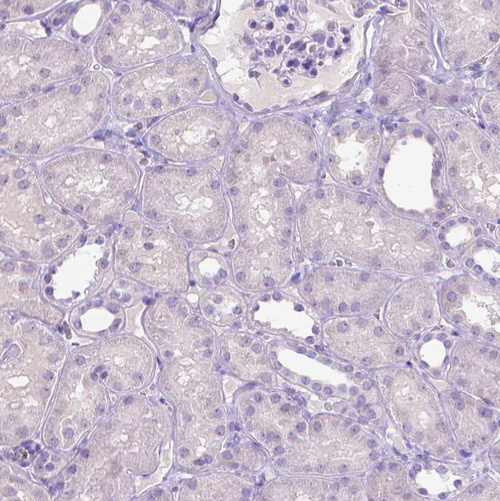

Immunohistochemistry analysis in human small intestine and skeletal muscle tissues using HPA064001 antibody. Corresponding SLC35C1 RNA-seq data are presented for the same tissues.